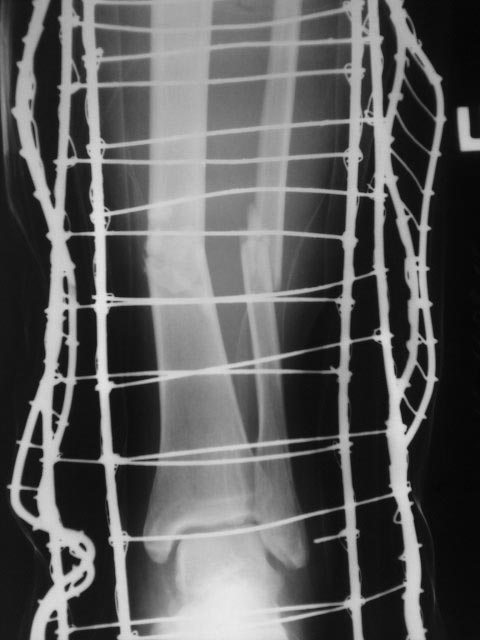

Здравствуйте! Спасибо за предоставленные снимки! Если судить по снимкам, то перелом сросся (костная мозоль со всех сторон). Необходима трансформация (уплотнение) костной мозоли, а для этого нужны нагрузка и время. Удаление пластины освободит наружный кортикал и распределит нагрузку равномерно по всей окружности кости. Что касается аутопластики, то она не показана при гипертрофическом псевдоартрозе. Ещё раз спасибо!

По данным рентгенограммам - перелом сростается. Исключить сомнения - сделать МСКТ. Если на МСКТ - данных за ложный сустав нет, то удалить металлоконструкцию и пользоваться ортезом на голень до достижения более прочной костной мозоли по данным контрольных R-грамм.

Еще бы понятно околосуставной, но зачем диафизарный перелом tibia в наши дни синтезировать пластиной?

Периостальная спайка вроде там все-таки есть. Наверно, ничего не надо делать. Или далить ближайшие к перелому винты, чтобы не было концентрации напряжений.

Доброго дня, Олег... Случай интересный. Непонятно расположение пластины( наружная установка имеет конкретные узкие показания) и выбор и количество винтов. В тактике, скорее соглашусь с доктором Челноковым, но если не уберете ближайшие к зоне перелома блокированные винты, скорее всего произойдет перелом конструкции. Уберите, может перелом срастется в условиях относительной стабильности. А пластика в этом случае, конечно не показана...